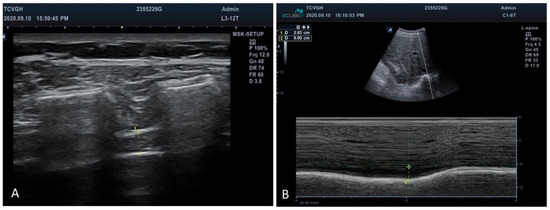

- Sarwal, A.; Walker, F.O.; Cartwright, M.S. Neuromuscular ultrasound for evaluation of the diaphragm. Muscle Nerve 2013, 47, 319–329. [Google Scholar] [CrossRef]

- Epelman, M.; Navarro, O.M.; Daneman, A.; Miller, S.F. M-mode sonography of diaphragmatic motion: Description of technique and experience in 278 pediatric patients. Pediatr. Radiol. 2005, 35, 661–667. [Google Scholar] [CrossRef]

| Sonography evaluation | |

| Diaphragmatic thickness fraction | 39.38 ± 28.50 |

| Diaphragmatic excursion (cm) | 3.00 ± 1.10 |

| Sonography evaluation | |||

| Diaphragmatic thickness fraction | 39.38 ± 28.50 | 56.40 ± 28.16 | <0.001 ** |

| Diaphragmatic excursion | 3.00 ± 1.10 | 3.83 ± 1.31 | <0.001 ** |